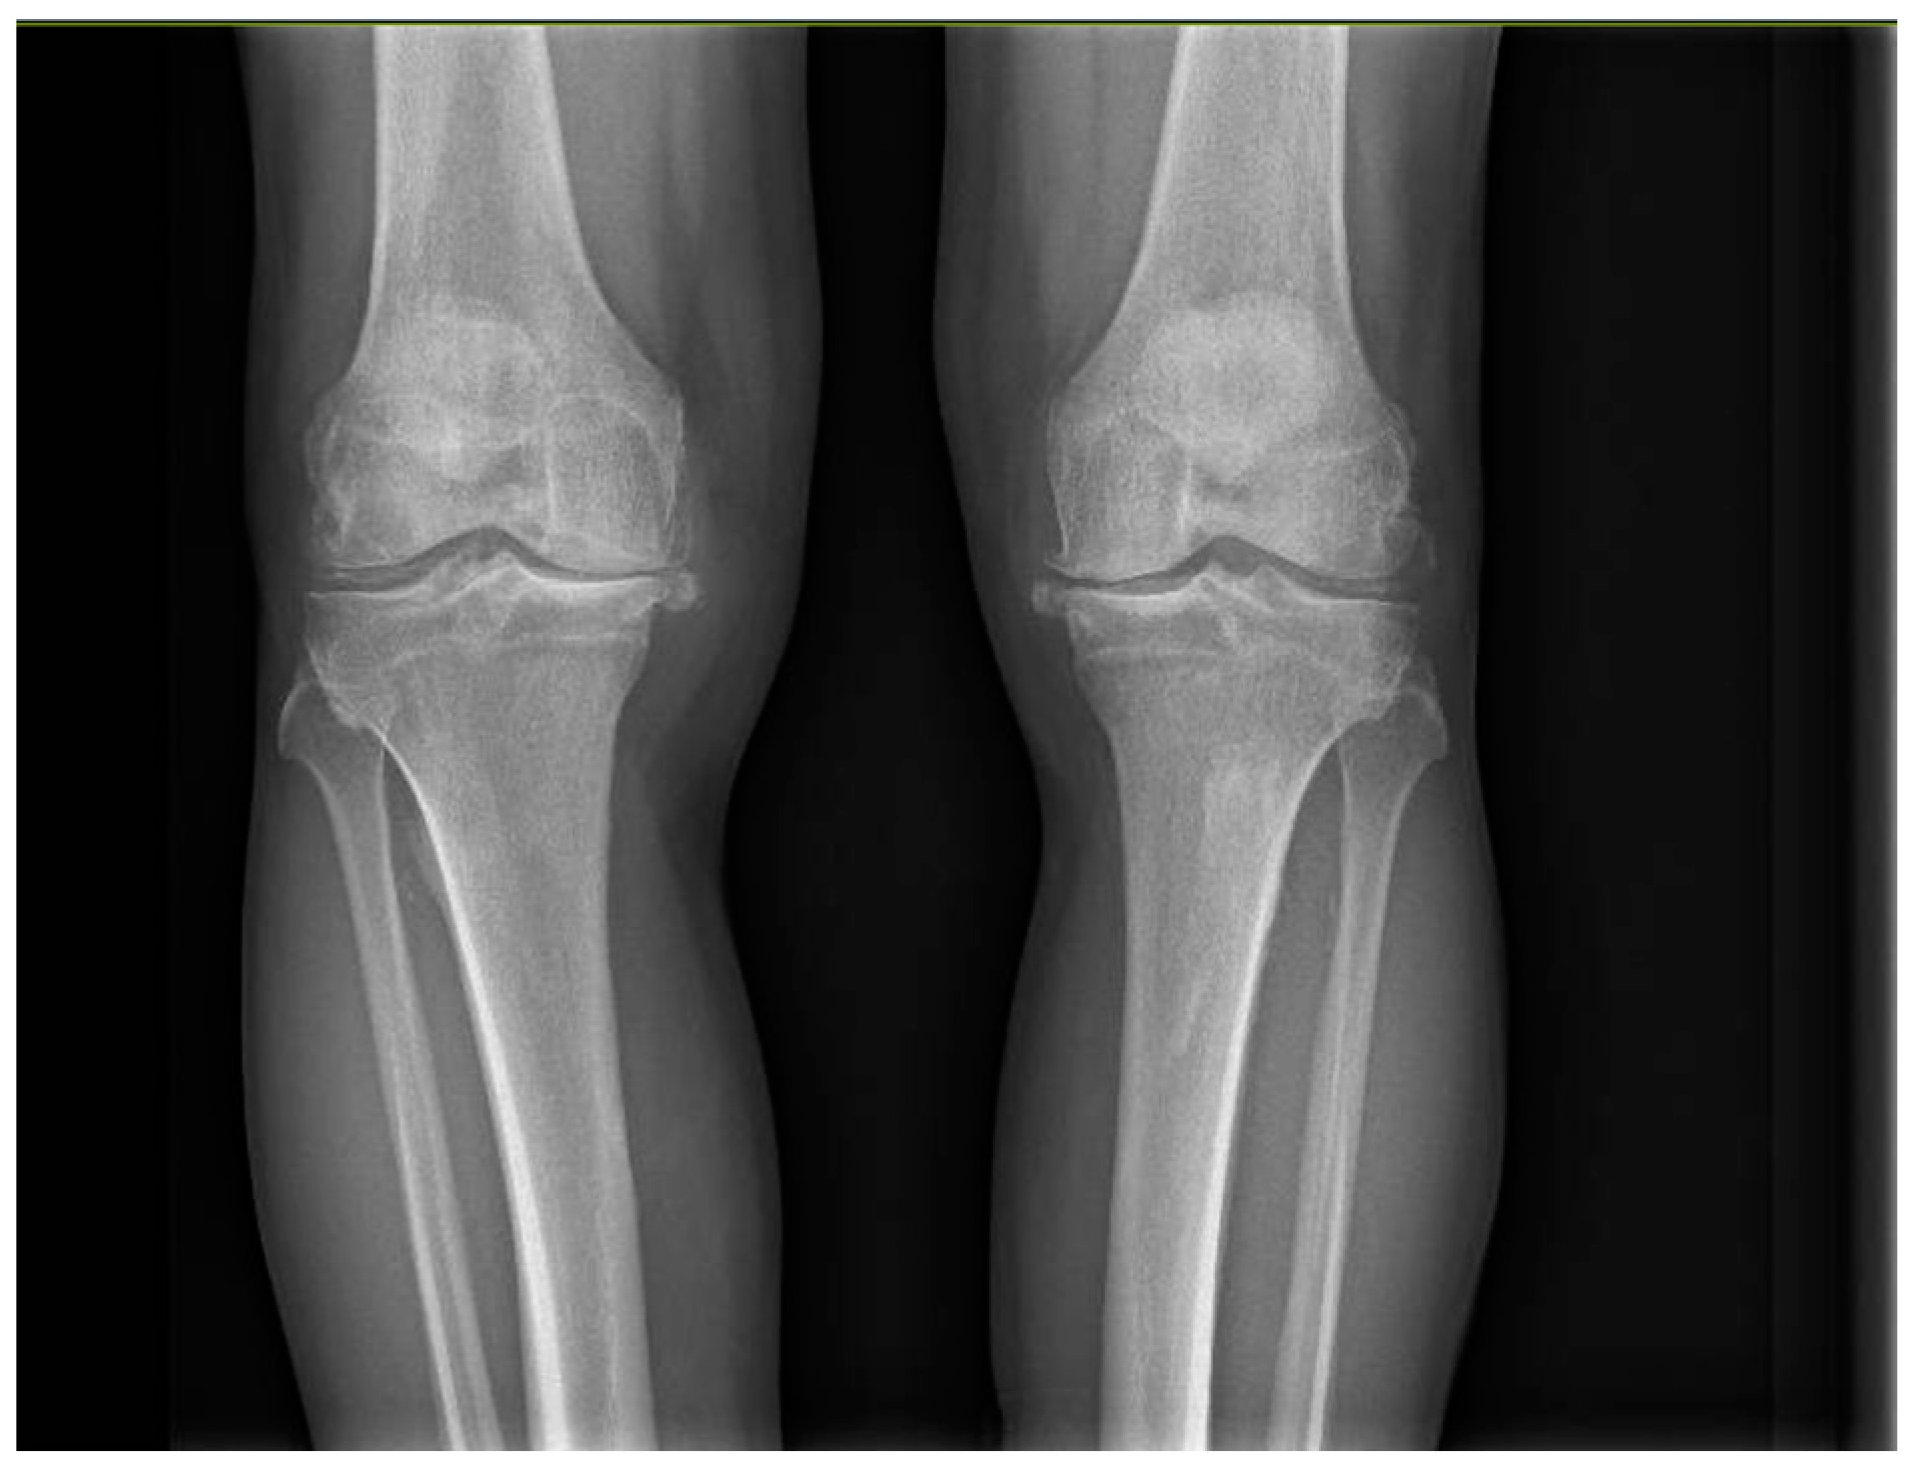

All patients had an indication for bilateral surgical treatment from the outset, with a Kellgren–Lawrence score of 3 or 4 (Figure 1), without previous knee replacement surgeries. Patients with unicompartmental knee replacements, complicated prostheses, secondary arthritis due to systemic or post-traumatic disorders, and with coagulation disorders were excluded.

Figure 1. Severe bilateral osteoarthritis of the knee.

The knee is the joint most affected by osteoarthritis, accounting for almost four-fifths of patients worldwide [1]. Osteoarthritis is a chronic irreversible condition that progressively becomes resistant to conservative treatments, such as pharmacotherapy and physiotherapy. Joint replacement surgery remains the only definitive approach to control symptoms and improve patient’s quality of life [2]. Today, total knee arthroplasty (TKA) is a routine procedure in orthopedic surgery to restore function in cases of severe osteoarthritis or systemic diseases. Diagnosis is mainly radiographic. The stage of knee osteoarthritis can be determined through one of the most widely used radiographic classifications: the Kellgren–Lawrence classification, which describes osteoarthritic joints in four stages of severity based on morphostructural changes [3].